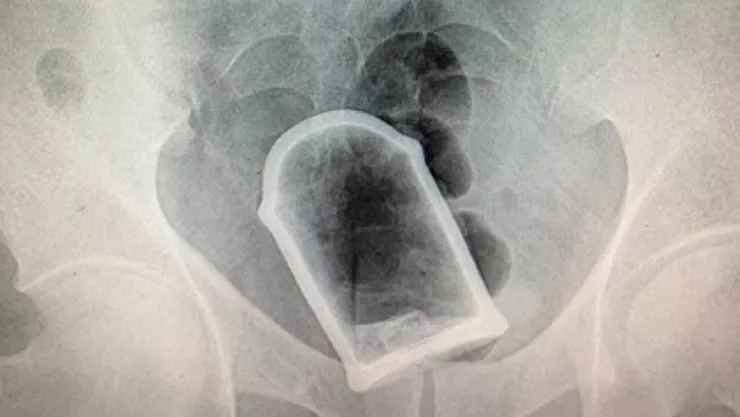

También revelaron que la mayoría de los objetos introducidos por esta vía son juguetes sexuales, tales como vibradores, incluso canicas y pelotas.

Estos casos han salido a la luz en los últimos años. En Toulon, Francia, un hombre de 88 años llegó con una bomba en el recto, un proyectil de artillería de la Primera Guerra Mundial por lo que el Hospital Sainte Musse fue evaduado.